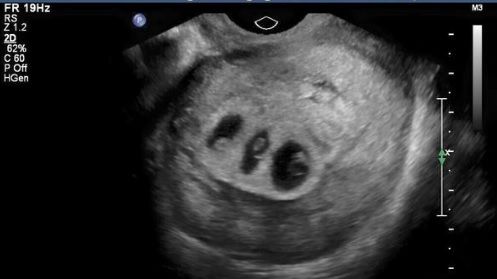

Soarta a făcut ca, în scurt timp, Chloe să rămână însărcinată. Nefiind la prima sarcină, tânăra a mers, prevăzătoare, la control, pentru a se asigura că bebeluşul este bine. La scurt timp după ce a păşit în cabinet, doctorul i-a dat o veste care a şocat-o! Ecografia îi arăta că urma să aducă pe lume încă trei bebeluşi!

În săptămâna 28 de sarcină, Chloe a mers la un nou control. A aflat atunci că avea în pântec doi băieţi şi o fetiţă. Din nefericire, nu era singura veste pe care aveau să i-o dea medicii... Fetiţa era slab dezvoltată şi toate semnele indicau că nu va supravieţui... Disperaţi, medicii au căutat o soluţie pentru a salva viaţa fetiţei. La un moment dat, au găsit-o, dar asta însemna ca mama să intre imediat în operaţie. Procedura, însă, punea viaţa băieţilor în pericol. Astfel, Chloe s-a văzut pusă în situaţia în care trebuia să aleagă care dintre cei trei copii va supravieţui: fetiţa sau băieţii?